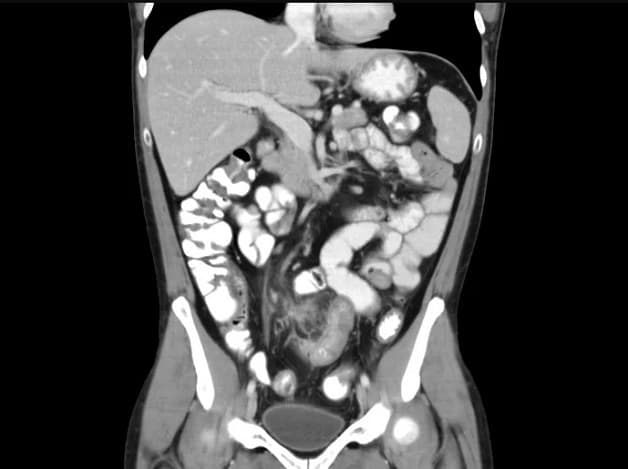

Hình ảnh chụp CT ổ bụng